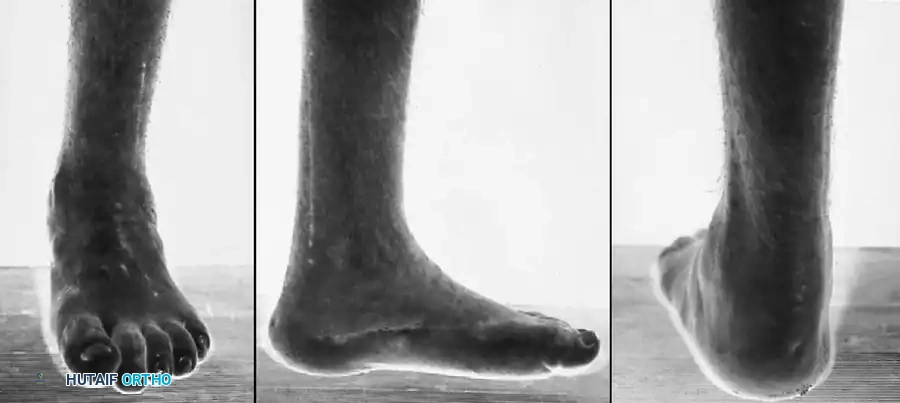

Clinical presentation of severe cavovarus foot deformity characteristic of Charcot-Marie-Tooth disease, demonstrating profound intrinsic wasting and hindfoot varus.

Fig. 32-18 Cavovarus foot deformity in Charcot-Marie-Tooth disease. A, Clawing of left great toe. B, Fixed varus deformity of left hindfoot. C, Supination and cavus deformity of forefoot.

Further clinical views demonstrating the classic "tripod" weight-bearing mechanism and severe forefoot pronation.